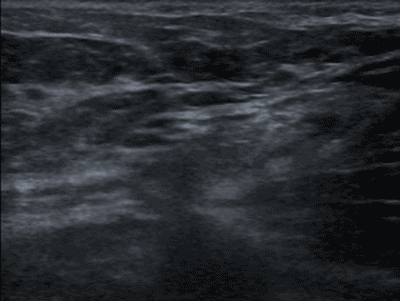

Ultrasound (US) uses sound waves to create harmless dynamic images (see Ultrasound Technique). It is quick, non-invasive, and nearly always available. US is especially useful for imaging soft tissue and is effective for assessing the abdomen, breast tissue, the scrotum, the neck or the skeletal/musculoskeletal system. It is a dynamic form of imaging where, for example, peristalsis of the intestines, mobility of a structure (e.g. a stone in the gallbladder or inguinal hernia) and compressibility of a structure (e.g. appendix, gallbladder, or veins in the upper or lower extremities) can be seen. See figure 4.

Ultrasound; inguinal hernia

Figure 4. Inguinal hernia (US performed during Valsalva maneuver followed by compression with the probe).